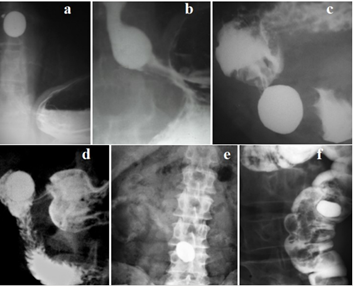

From a functional point of view, the stomach is divided into proximal and distal parts. The proximal part, including the fundus and the body of the stomach, provides reception and temporary storage of food. It regulates intragastric pressure and stimulates the tonic advancement of the chyme into the distal part. In addition, it provides space and time for pepsin and hydrochloric acid to act in the early stages of digestion. The fundus is characterized by tonic rather than peristaltic contraction.12 An important function of the proximal stomach is its ability to accommodate. More than a liter of food can enter the stomach without increasing intragastric pressure. A study of pressure on volunteers showed that intragastric pressure decreases moderately after eating and returns to the initial level as soon as solid food ingredients penetrate the duodenum.13s The motor function of the proximal stomach is regulated by reflexes: receptive relaxation and gastric accommodation. Receptive relaxation is manifested by a decrease in the tone of the proximal stomach during swallowing. For example, Shafik's study showed that «Pharyngeal distension produced a significant pressure drop of the corpus of the stomach (p < 0.05); the pyloric antrum shows no response. Upper, middle, or lower esophageal distension produced gastric response like that evoked by pharyngeal distension".14 Stomach accommodation is described as a relaxation reflex of the proximal stomach in response to distension. Unlike receptive relaxation, this reflex does not depend on the stimulation of the esophagus and pharynx. The method of evacuation of stomach contents depends on body position and volume of contents (Figure 2).

Figure 2  Stages of evacuation of the stomach in a vertical position. (a). The level of hydrostatic pressure (h) is sufficient to open the pyloric sphincter (pS).  (b). When part of the contents of the stomach was evacuated into the intestine and the hydrostatic pressure decreased, pS is closed. In the antrum the peristaltic waves of the lesser and greater curvature of the stomach are converged, blocking the lumen of the stomach. A closed antral cavity (A) has developed between this antral sphincter (white arrow) and pS. The advancement of the peristaltic wave leads to an increase in pressure in the antral cavity. When it reaches the threshold pressure, the pS relaxes and the bolus enters the duodenal bulb. Normally, the volume of the bolus corresponds to the capacity of the duodenal bulb.